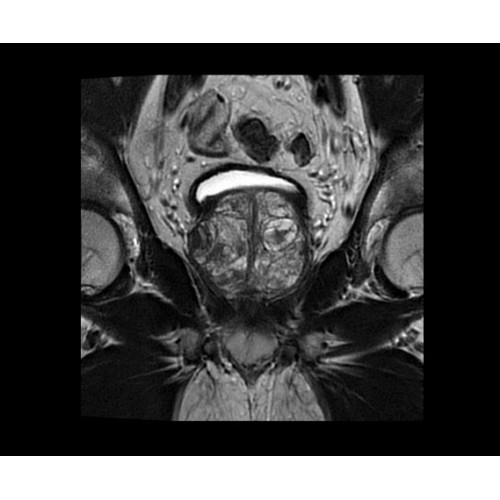

SIGNA PET/MR 3.0T — это гибридная система, в которой совмещаются две принципиально разные технологии — магнитно-резонансную томографию (МРТ) и позитронно-эмиссионную томографию (ПЭТ). Система отличающийся высокой чувствительностью и эффективностью и предназначена для диагностики в области онкологии, неврологии, кардио-васкулярных исследований, исследований воспалительных процессов.

Компания GE Healthcare представляет революционную, полностью интегрированную систему SIGNA PET/MR1, в которой сочетаются времяпролетная технология (TOF) и возможности напряженности магнитного поля 3.0 Тл. Мы поможем вам поднять исследования на более высокий уровень. SIGNA PET/MR позволяет достичь впечатляющей точности и скорости исследований, а благодаря новейшей технологии реконструкции Q.Clear2 качество изображений улучшается в два раза. Кроме того, в систему включен полный набор клинических приложений и гибких катушек для проведения любых видов исследования, открывая для вас возможности визуализации, о которых вы даже не догадывались.

• TurboTOF — инновационная технология позволяет корректировать коэффициент затухания сигнала и минимизировать потери анатомических данных, создавая МР-систему для количественной визуализации.

• Q.Clear — в основу технологии легли накопленные знания о том, как минимизировать помехи при реконструкции и получить четкое изображение. При значительном улучшении качества изображения сохраняется точность расчетов. Сочетание технологии TOF и реконструкции Q.Clear — ваш надежный помощник для получения точных и достоверных данных.

• МРТ с функцией нулевого времени эхо (ZTE) отличается точностью, возможностью персональных настроек и отсутствием ионизирующего излучения. Она приходит на смену традиционному исследованию на основе рентгеновского излучения. МРТ с функцией нулевого времени эхо (ZTE) на базе SIGNA ПЭТ/МРТ является более надежной и быстрой по сравнению с системами, использующими сверхмалое время эхо (UTE).